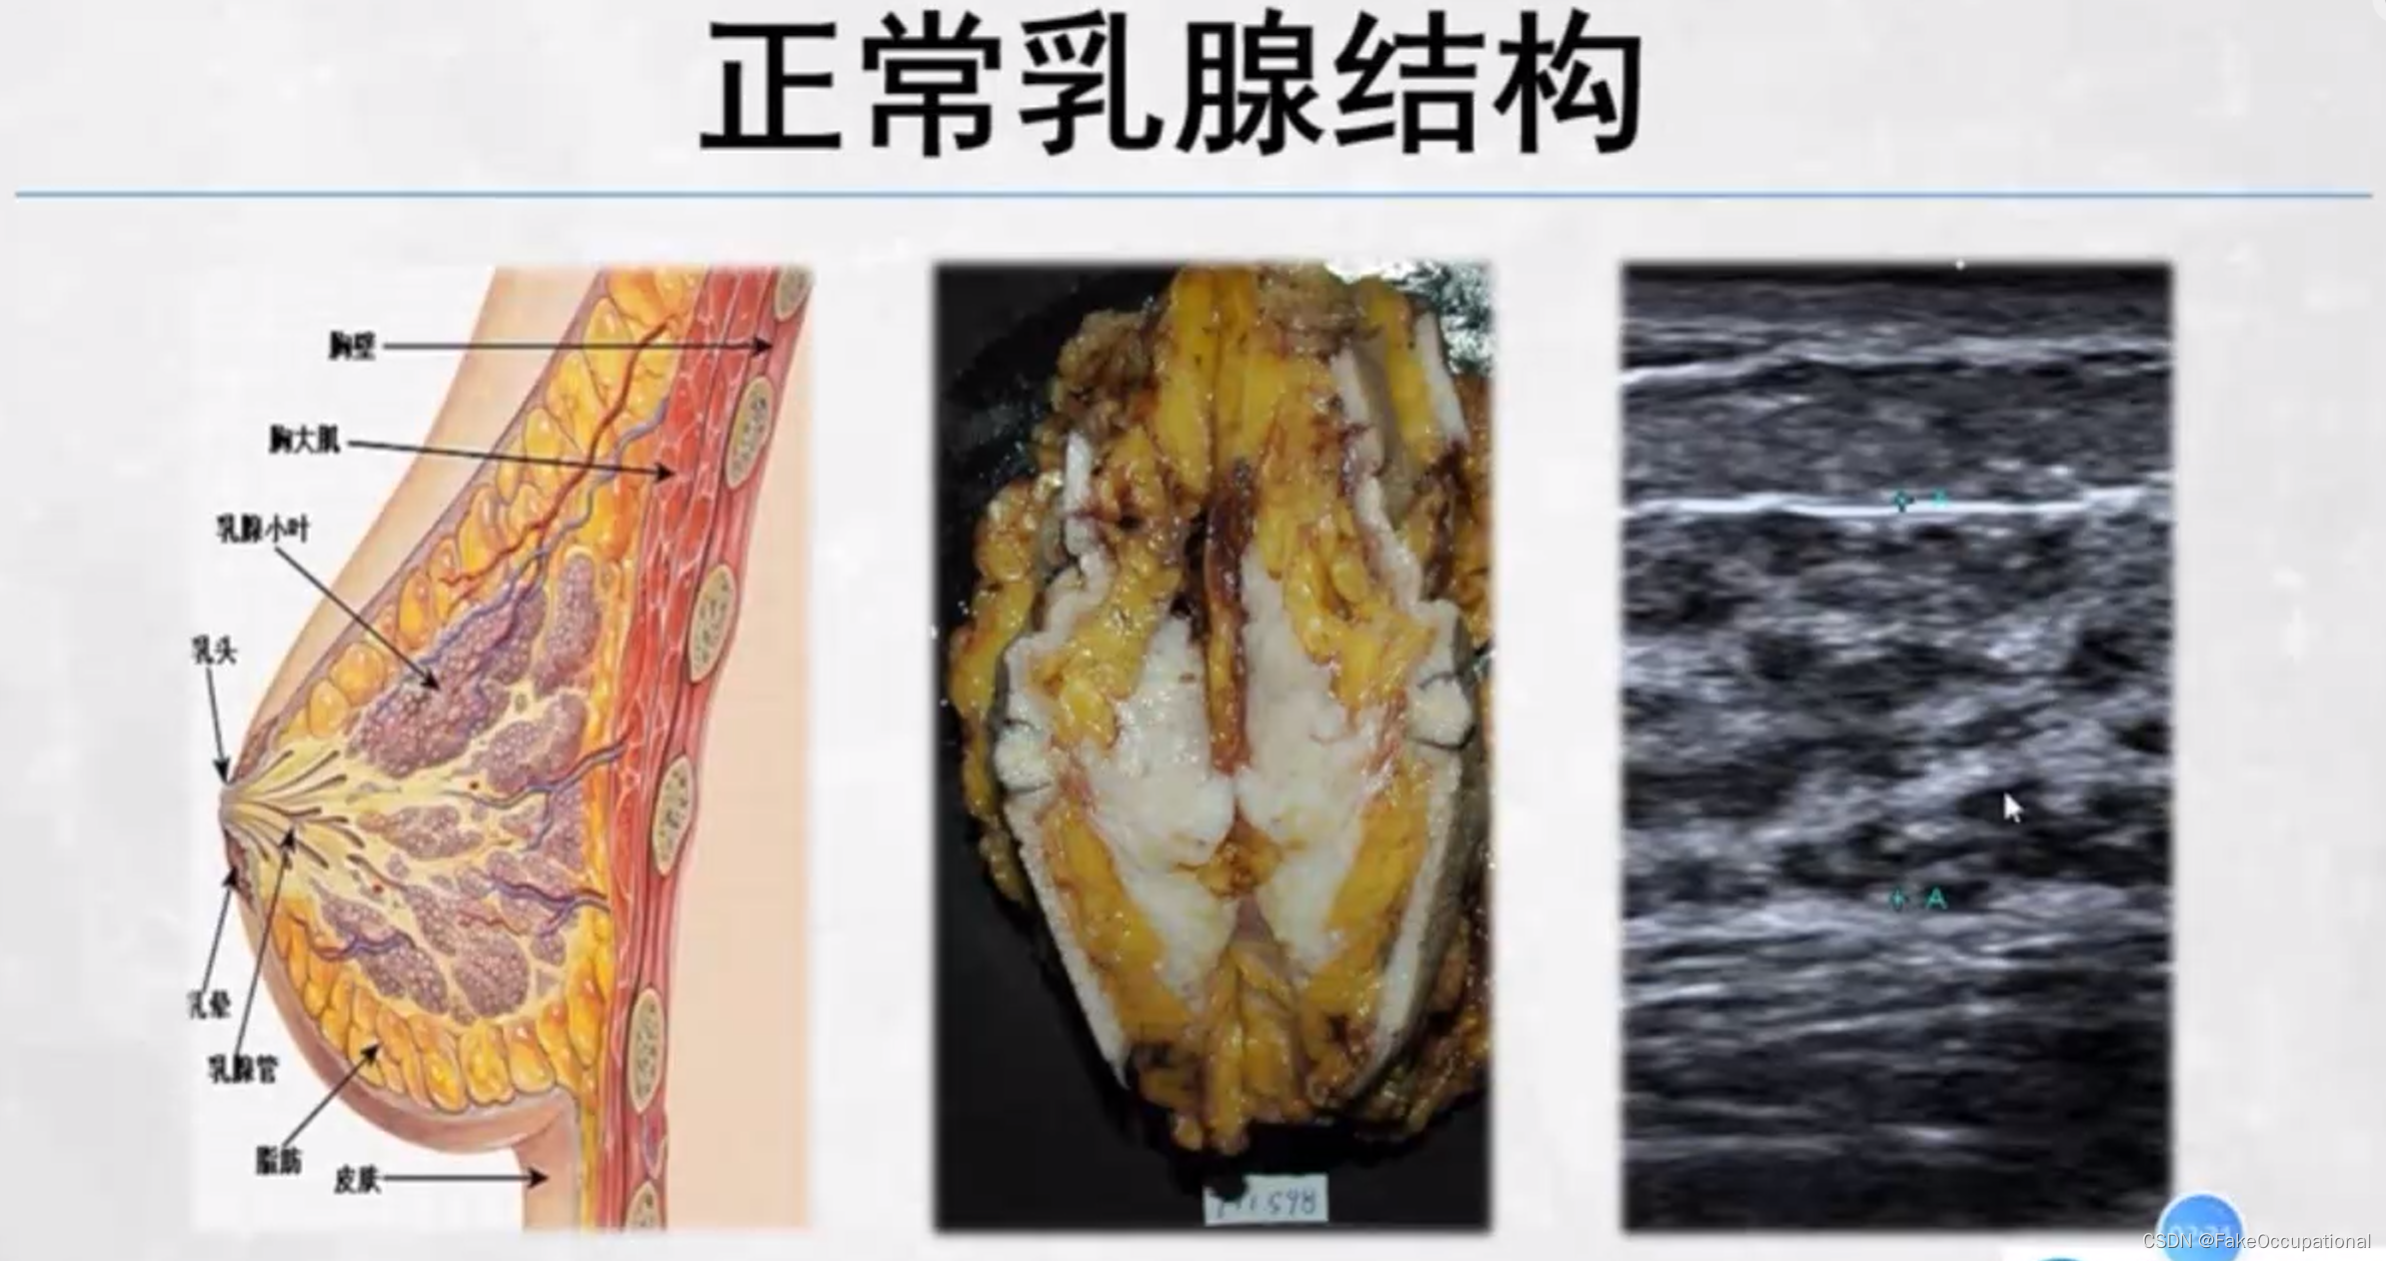

乳腺的生理解剖概要

乳腺的生理解剖概要